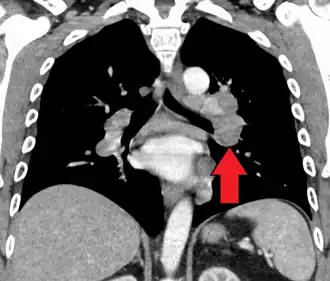

-

Hilar adenopathy especially on the person's left (coronal CT) -